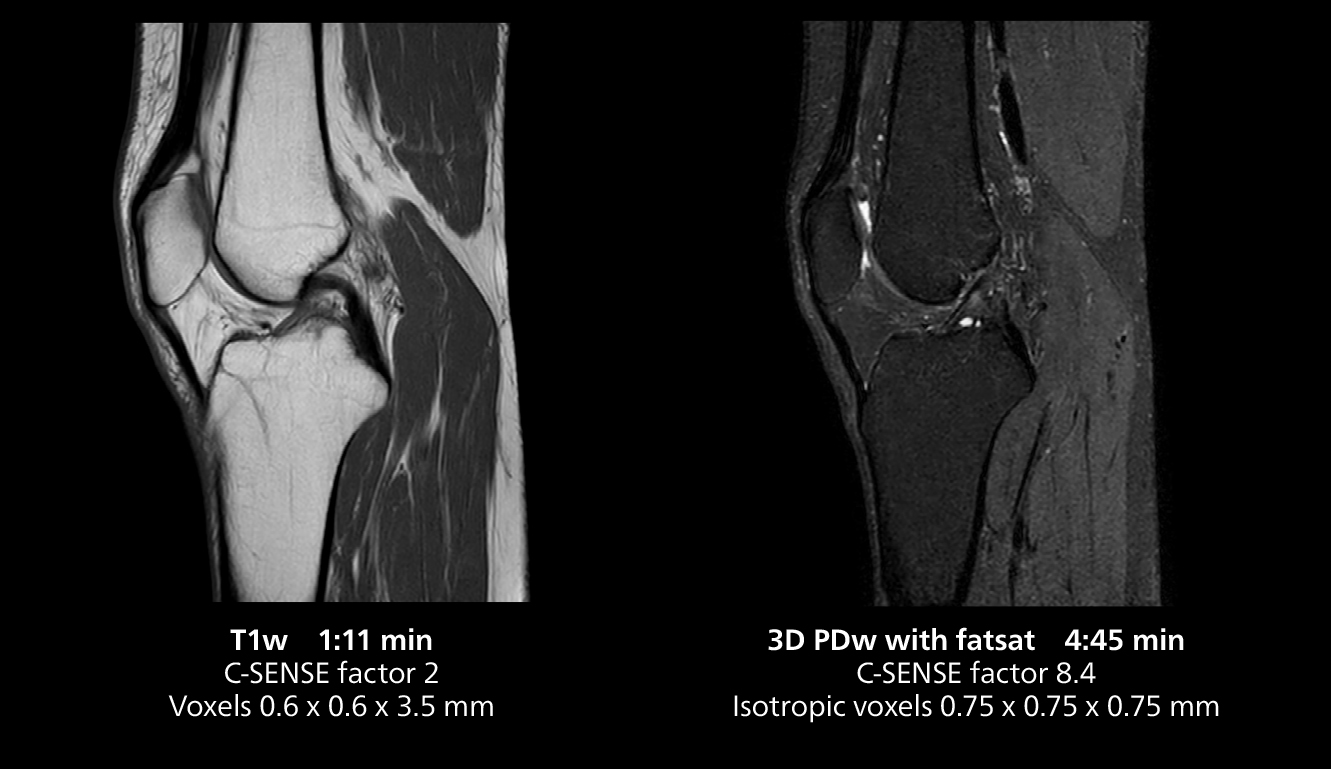

According to Dr. Gellée, the hospital conducts an average of four studies each hour, totaling about 40-45 patients per day on their MR 5300. Studies are read by approximately 50 radiologists in the Bordeaux area. Dr. Gellée is especially satisfied with the image quality of the MR system. "I obtain higher image contrast and more anatomical precision than I was used to,” she says. “When I am able to choose, I request that studies be done on this system, because I get better anatomical image quality. For example, in the knees, I can get great images of the meniscus. To me, it looks as pretty as 3T.”

The isotropic high resolution 3D sequence in this MRI case allows for reformatting to obtain other orientations with high quality. Acquired on the MR 5300 system.

“We have more speed in 3D sequences,” Dr. Gellée states. “With Compressed SENSE, we can replace two or three 2D scans withone high-quality 3D scan. High quality additional orientations are then obtained by post-processing of the 3D data set, thus saving scanning time.”